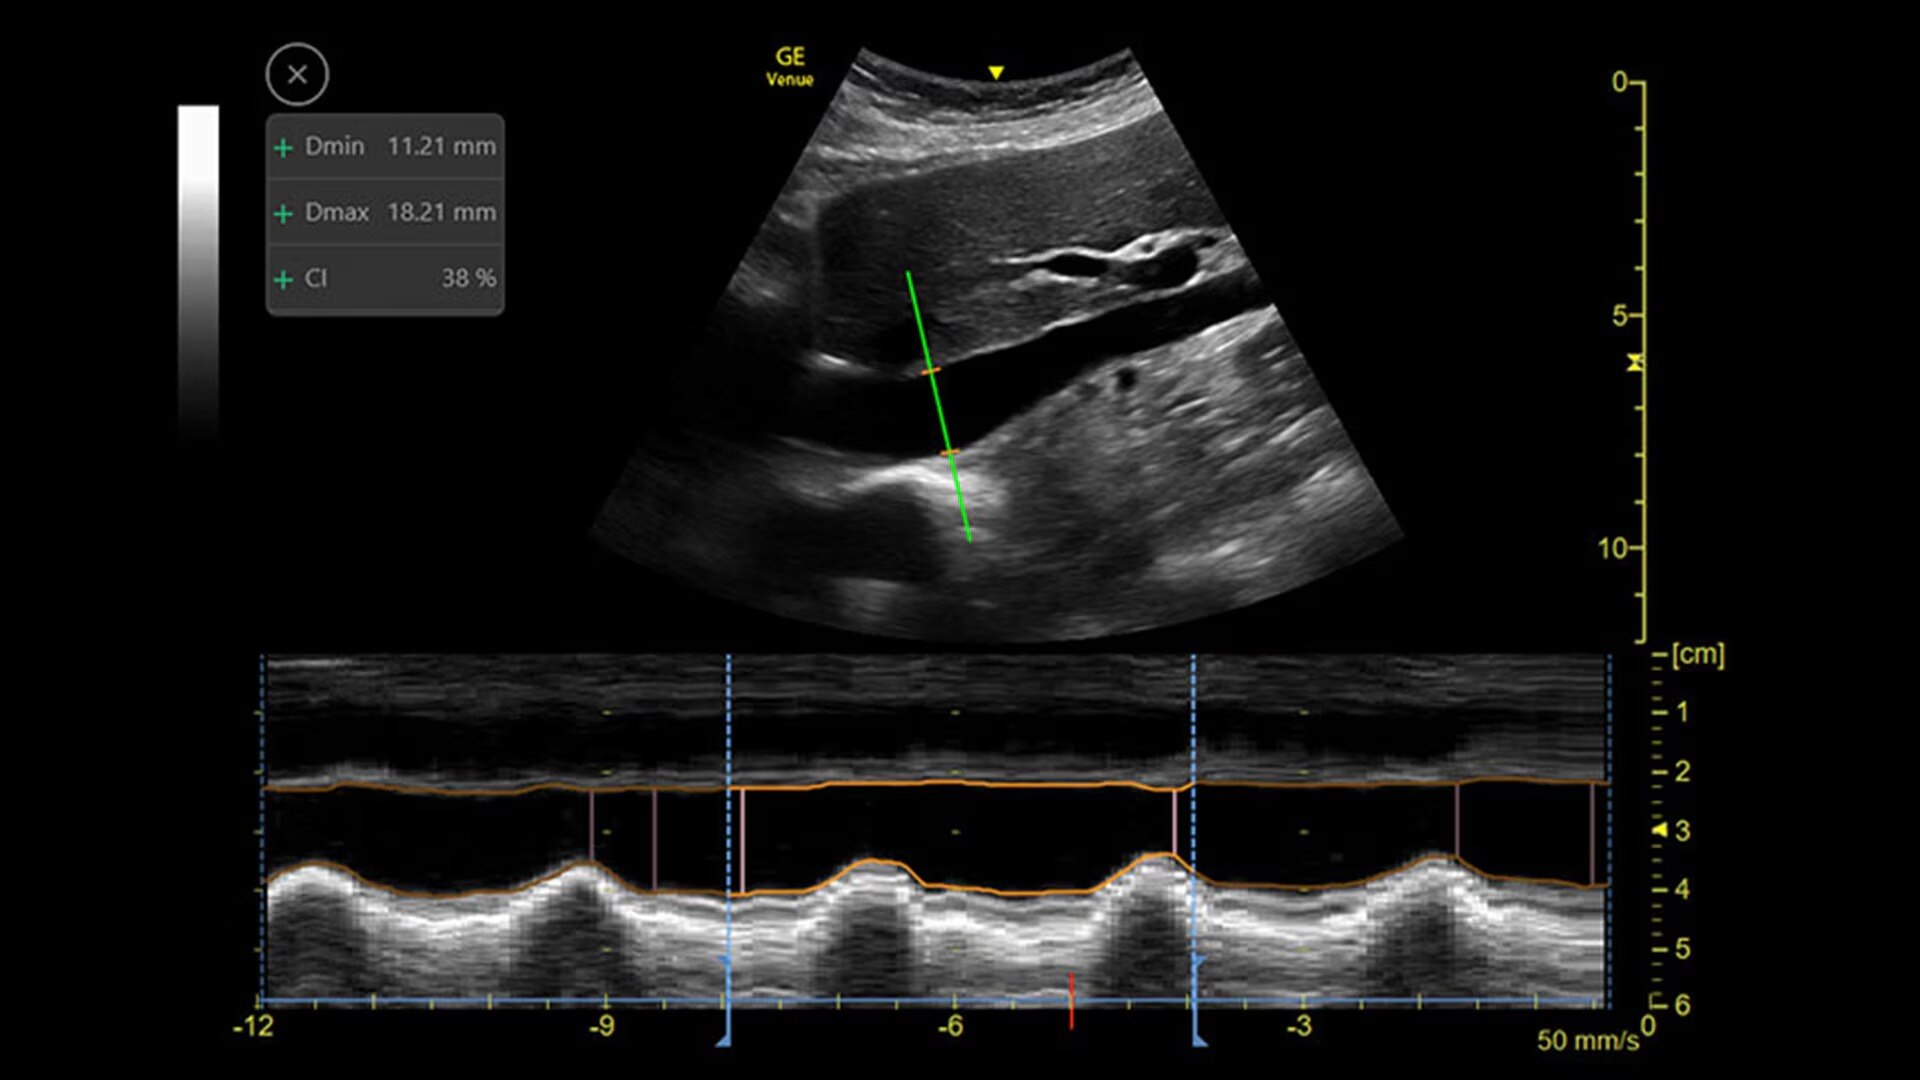

Catheter to Vessel Ratio

Accurate catheter selection tool

Selecting the wrong sized catheter can lead to catheter related thrombosis.3 Catheter to Vessel Ratio is a measurement tool that supports clinicians in selecting the appropriate sized catheter based on vessel diameter.